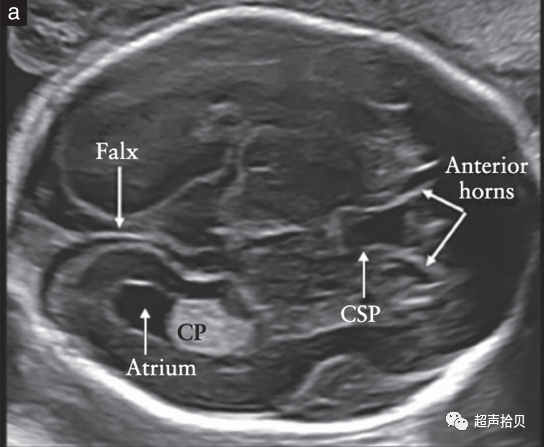

图2胎儿头部的横切面,显示标准的经脑室(a)、经小脑(b)和经丘脑(c)扫描平面。经脑室和经丘脑平面允许评估大脑半球区域的解剖完整性。经小脑平面允许评估后颅窝的小脑和大池(CM)。CP-脉络膜丛、CSP-透明隔腔、TH-丘脑。

大脑

用于胎儿大脑基本检查的标准扫描平面在更新的 ISUOG 指南20中有描述。两个横断面,通常称为经脑室平面和经丘脑平面,可以显示与大脑解剖完整性相关的大脑结构(图 2)。成像伪影掩盖了近端半球(更靠近探头的半球)。应添加第三个横断面-经小脑平面来评估后颅窝。应评估以下大脑结构: